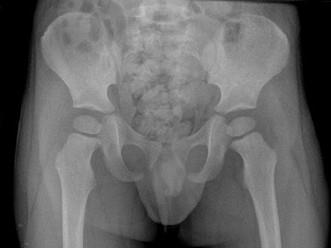

男,请根据其正常骨盆影像图像,判断其最可能的年龄 ( )A、11岁左右B、14岁左右C、5岁左右D、8岁左右E、2岁左右

问题 男,请根据其正常骨盆影像图像,判断其最可能的年龄 ( )

选项 A、11岁左右 B、14岁左右 C、5岁左右 D、8岁左右 E、2岁左右

答案 E